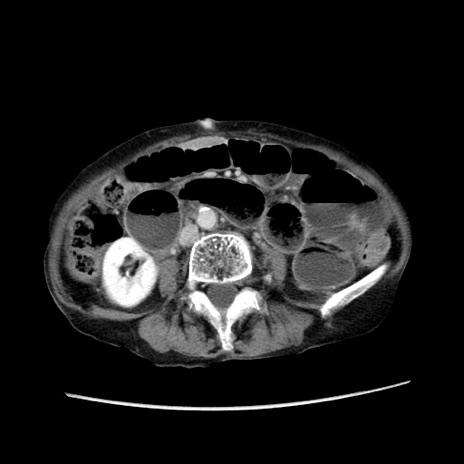

冠状断像

症例25(横断像)

【症例】80歳代女性

【主訴】胸のつかえ感

【現病歴】約9時間前に食後から胸のつかえた感じあり、嘔吐あり、来院。

【既往歴】胃癌(全摘)、胆摘、虫垂炎

【身体所見】心窩部に圧痛あり、反跳痛なし。

【データ】WBC 5700、CRP 0.05